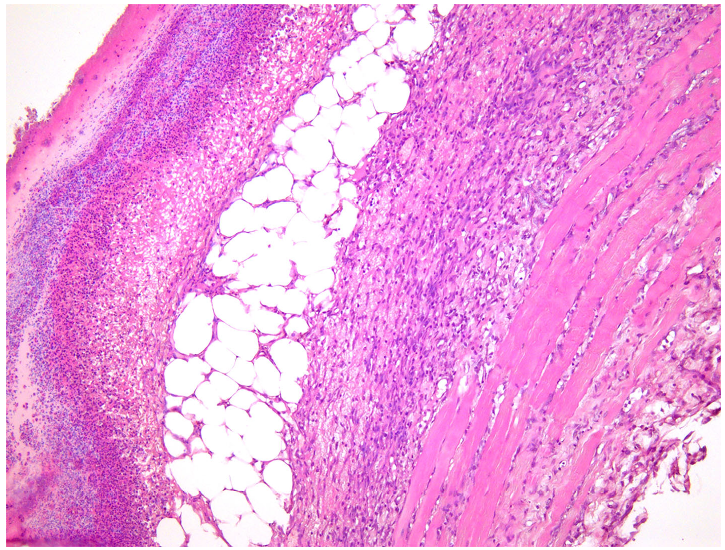

—fibrin clot,

—granulation tissue,

—adipose tissue.